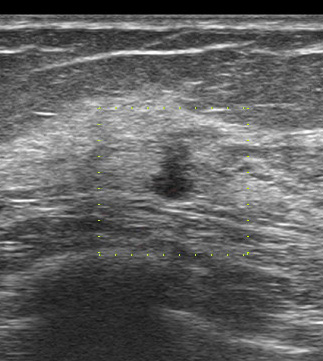

例として今週のコラム526回目に登場したAさん

昨年 検診で(昨年にはなかった)シコリが指摘されたのだが、(なんと!)カテゴリー2として要精査とならずに、一年後(今年)同じシコリが(今度は、少し大きくなったからと)漸く要精査となり当科をつい先日受診された。

それともう一つ、初回(昨年要精査としなかった)エコーが検診機関から送られてきたよ。

初回の検診エコー(今回送られてきたもの)

縦長! 不整型!

これ(去年に何もなかったのに、しかも60歳代)で要精査に何故しない!!

別角度

やっぱり、どう見ても「癌疑い」

何で、カテゴリー2で要精査としなかったのだろう。

検診機関なので「当然」エコーは技師が行っています。